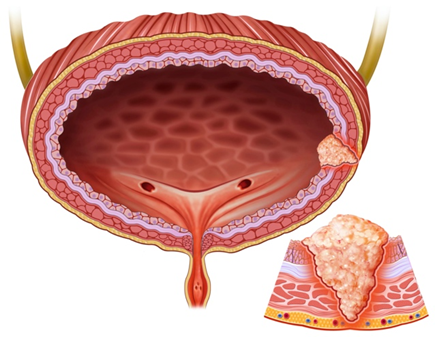

Mesane Kanseri

Mesane kanserinin erken tanı ve etkin tedavisi.